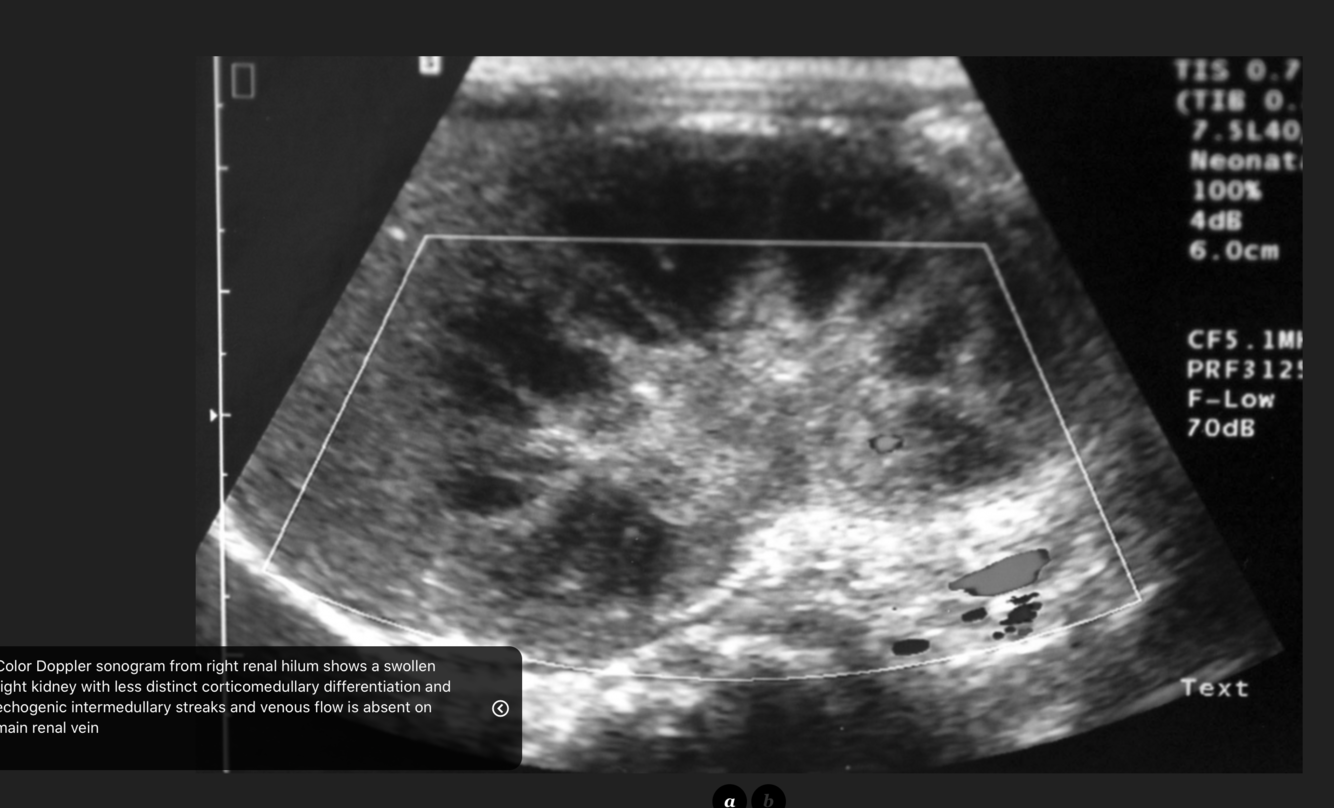

What are the signs of renal vein thrombosis in the kidneys on USS?

Early and late phases

Kidneys